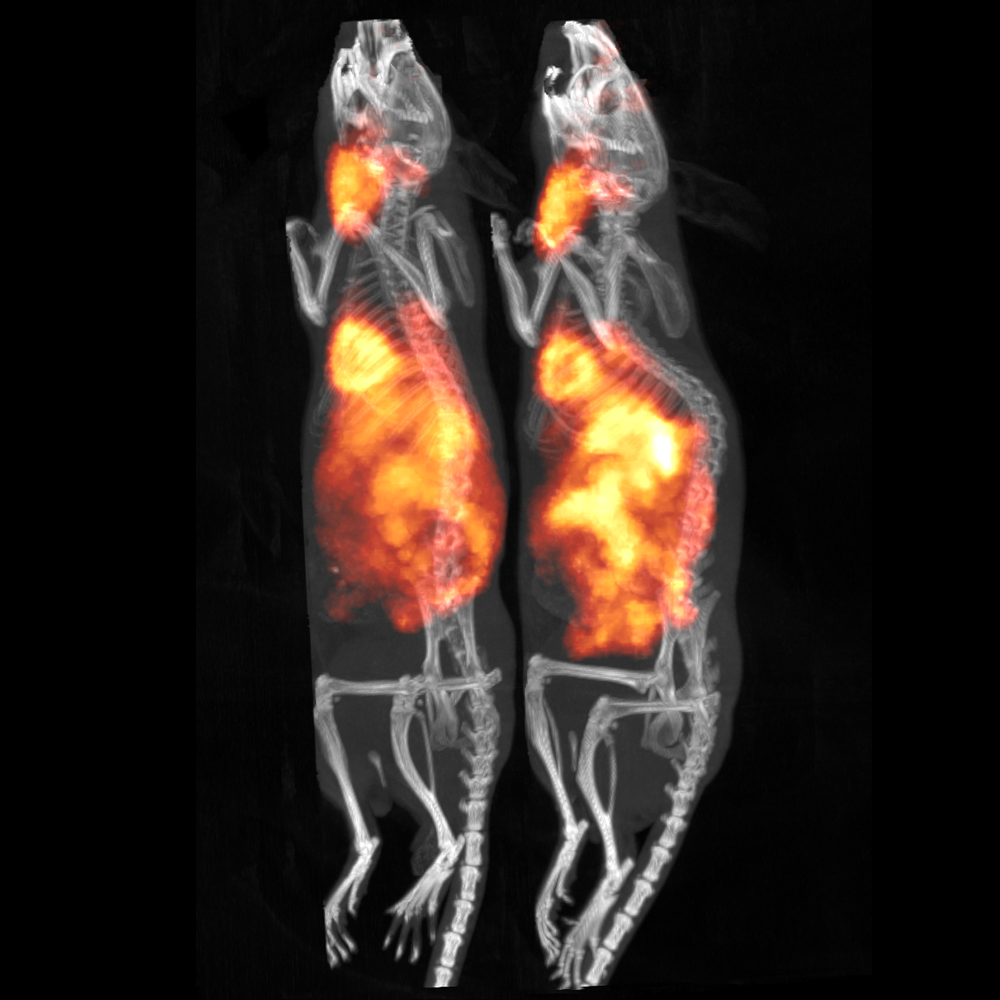

リング径が大きいため、複数匹のマウスや大型動物のイメージングが可能です。また、リアルタイムのモンテカルロ・シミュレーションに基づく独自のTera-Tomo™ 3D逐次均一画像再構成により、全視野にわたって均一な画質が得られます。

- 個々の被験動物の生理学的モニタリングが可能な複数動物の同時イメージング (最大 マウスx4 匹またはラットx2匹)

60 g マウス x 4匹 または、300 g ラット x 2匹 |